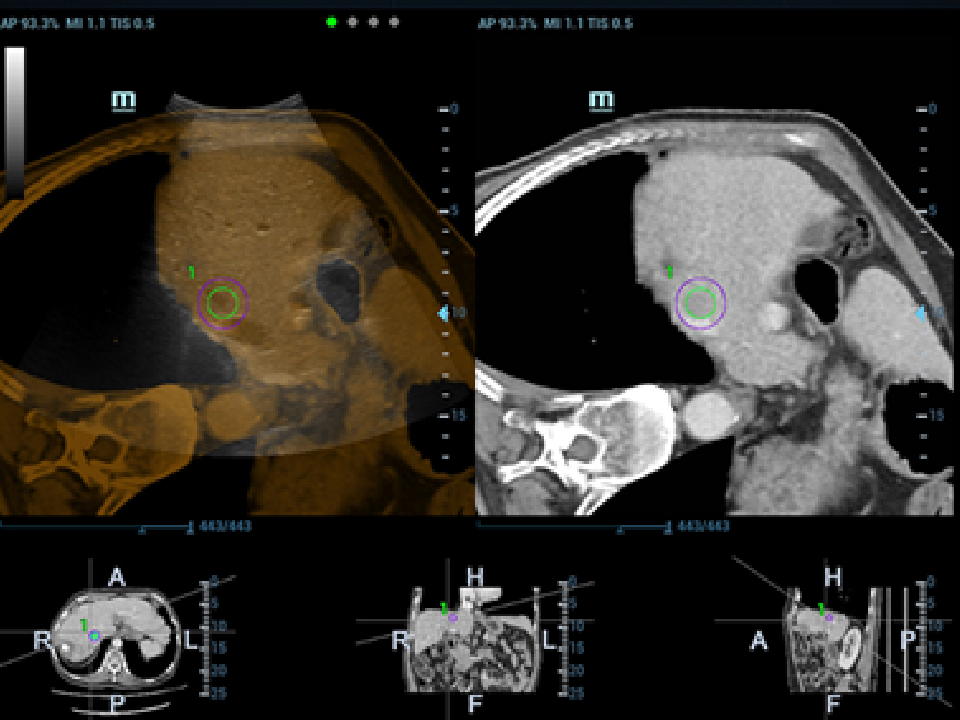

eXceptional Intelligence

Intelligence throughout entire workflow

Intelligence integrated in professional diagnostic tools for whole examination procedures,DC-80 with X-Insight provides exceptional intelligence integrated in professional diagnostic tools across wide applications and throughout whole examination procedures, from regular screening to further diagnosis and clinical follow up.

iNeedle

ItŌĆÖs the 2nd generation needle enhancement technology with automatic angle adjustments for easy needle approach to target and enhanced accuracy during guided procedures.